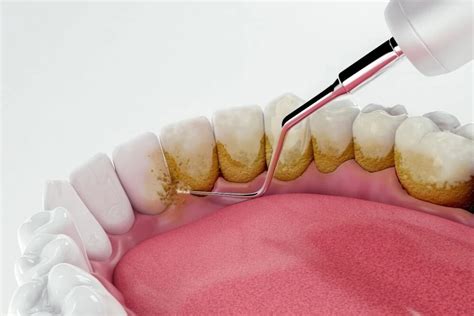

- Ultrasonidos: El empleo de ultrasonidos es especialmente útil cuando el sarro está ubicado por encima de la línea de las encías (unión del diente con la encía). Logran desprender el cálculo en fragmentos sin dañar la superficie dentaria. Es muy importante que el proceso sea profusamente refrigerado con agua, pues los ultrasonidos producen un aumento térmico que podría causar dolor y daño en la estructura dentaria.

- Curetaje: Las curetas dentales son dispositivos manuales con formas muy variadas, de tal manera que consiguen adaptarse perfectamente a la superficie de los dientes. Permiten llegar bien a los espacios que hay en el surco de la encía. Allí se acumula el denominado sarro subgingival, especialmente nocivo para los tejidos gingivales al estar colonizado frecuentemente por patógenos periodontales muy dañinos.

En Clínica Dental Letamendia, empleamos tecnología de ultrasonidos de última generación para quitar el sarro de los dientes de manera precisa y confortable. El proceso incluye también el uso de instrumental manual especializado (curetas) para el refinado de superficies radiculares y la eliminación de sarro en áreas de difícil acceso.